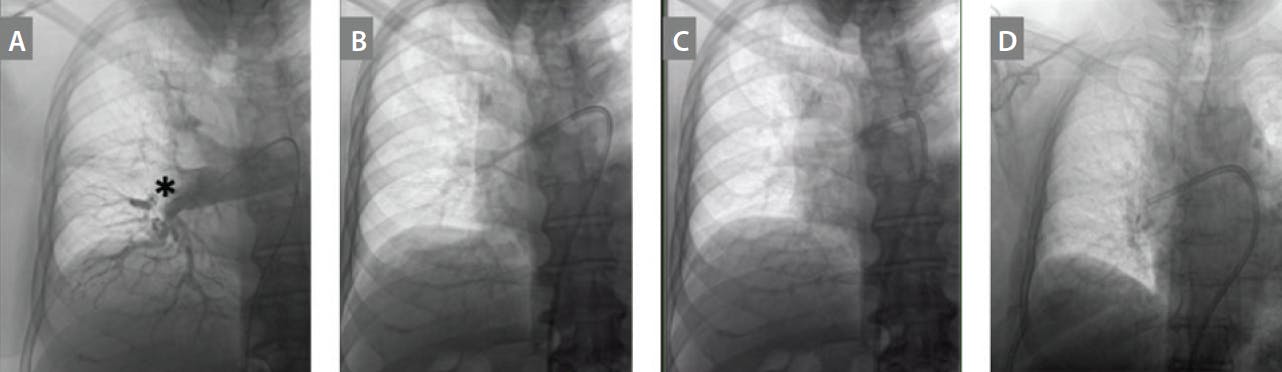

The Indigo Lightning aspiration system (Penumbra, Inc.) combines a sustained, continuous aspiration pump able to achieve near-pure vacuum (the Engine); a large bore, laser-cut flexible hypotube (the CAT12 catheter); and sensor-driven, intelligent aspiration flow regulation (Lightning). This aspiration system typically uses a ≥ 12-F common femoral vein (CFV) access. Access to the pulmonary artery (PA) can be achieved using a 7-F balloon-tipped catheter or a 6-F pigtail catheter. Pulmonary angiography is typically performed using the pigtail catheter to visualize the thrombus and the pulmonary vasculature (Figure 1A) either via the primary access or via a secondary venous access that would permit continuous hemodynamic monitoring. Initial ultrasound-guided access of the CFV is then obtained. A 0.035-inch, stiff, angled Glidewire or Glidewire Advantage (Terumo Interventional Systems) can be used to help direct the catheters to the main PA and distal segmental branches. Alternatively, a 0.035-inch Hi-Torque Supra Core guidewire (Abbott) can also be used to advance into the lobar branches.

Figure 1. The Penumbra Lightning Aspiration system for use in acute PE. Pulmonary angiography of the right main PA and associated lobar branches; the asterisk points out the thrombus (A). The Lightning 12 catheter over the Amplatz Super Stiff wire (B). The Lightning 12 catheter without the wire (C). The Lightning 12 catheter with the Separator that comes with the Lightning system (D).

Next, using either the pigtail catheter or a multipurpose catheter, a stiff wire such as a 0.035-inch, 1-cm-tip Amplatz Super Stiff short taper guidewire (Boston Scientific Corporation) is advanced through the catheter. The short sheath is then exchanged for a long sheath, which is placed into the main, right, or left PA. It is best to place the sheath above the pulmonary valve to avoid excess trauma with catheter exchanges, if performed. The preferred sheath is usually a 14- or 16-F X 65-cm Gore DrySeal Flex introducer sheath (Gore & Associates). Using a larger sheath allows for the Lightning 12 device to torque freely and prevents shearing of thrombus if using the XTRACT technique.2 The Lighting 12 catheter is then advanced over the wire to the desired location, and aspiration is performed using continuous aspiration (Figure 1B). The HTORQ curve, a feature of the Lightning 12 catheter, has both a primary and a secondary curve, maximizing sweep within large pulmonary vessels and facilitating, access to acutely angulated vessels (Figure 1B). It is possible to advance the catheter without a wire to maintain maximal contact with the clot and remove wall-adherent thrombus, but caution must be taken to avoid damage to the PAs (Figure 1C). Continuously torquing the catheter using the wings just after the rotating hemostatic valve (RHV) can help prevent the tip of the catheter from getting stuck on the vessel wall.

Blood is then aspirated into a disposable canister, where solid material is strained. The Lightning 12 system uses a proprietary, computer-aided, flow regulation to minimize blood loss and maximize suction when on occlusive thrombus. Auditory (clicks) and visual cues (green flashing lights) suggest open flow and will trigger the operator to turn off aspiration using the manual flow switch. After adjusting the catheter location, the absence of audible clicks and a solid green light that eventually turns orange after > 20 seconds of occlusion suggests appropriate positioning for effectively aspirating thrombus. Pulmonary angiography can be performed throughout the procedure with a secondary pigtail or direct injection through the Lightning 12 catheter, using 10 mL contrast chased with 10 mL saline.

If the thrombus burden is large and organized, it is advised to use the mechanical Separator 12 (SEP12; Penumbra, Inc.), which is a polymer-jacketed bead attached to a guidewire. This is introduced through the RHV and advanced approximately 1 to 2 cm in front of the Lightning 12 catheter with rapid agitation to break up leading thrombus into smaller particles that can be aspirated (Figure 1D). Care must be taken to not advance the SEP12 blindly into vessels to avoid perforation. When pulmonary arterial perfusion and hemodynamics improve, the system can be retrieved or advanced into the contralateral side by repeating the steps. Venous closure is typically accomplished via a “figure-of-eight” or “purse-string” suture.